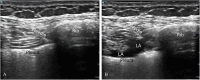

Background: Various regional analgesic methods are frequently incorporated into multimodal analgesia strategies for managing rib fractures. This study aimed to compare the analgesic efficacy of ultrasound-guided superficial serratus anterior plane block (S-SAPB) and intercostal nerve block (ICNB) in patients with isolated rib fractures.

Methods: This randomized controlled trial included patients aged 18-65 years with unilateral isolated rib fractures (≤ 6 ribs) resulting from trauma. Patients underwent ultrasound-guided S-SAPB (20 ml 0.25% bupivacaine) or ICNB (3 ml 0.25% bupivacaine for each fractured rib). Pain levels were assessed using the Visual Analogue Scale (VAS) both prior to the procedure (Pre-Block, (T0)) and at specific time points following the intervention: 1st hour (T1), 2nd hour (T2), 4th hour (T4), 8th hour (T8), 16th hour (T16), and 24th hour (T24). The changes in observed values over time were expressed as delta (Δ).